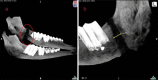

Objectives: To investigate the quality of newly formed bone in sheep mandibles submitted to distraction osteogenesis and low-level laser therapy (LLLT), based on hardness and modulus of elasticity values. The ideal moment for laser application (during the latency/activation period vs. during the bone consolidation period) was also evaluated. Computed tomography imaging was used to assess relapse as a result of early device removal.

Study design: Extraoral distraction devices were placed in five sheep so as to achieve 1.5 cm of lengthened bone in 60 days. Distraction devices were removed 50, 40, and 33 days after surgery. Four animals were treated with LLLT, at different times, and one was used as control (no LLLT).

Results: When applied during the bone consolidation period, LLLT caused an increase in hardness and modulus of elasticity values. On the other hand, animals irradiated with LLLT during the latency/activation period presented a delay in bone healing. A period of consolidation of 13 days (early device removal) was associated with relapse.

Conclusions: Nanoindentation tests were able to detect slight abnormalities in bone metabolism and proved to be important tools for the assessment of bone quality following distraction osteogenesis. LLLT provided increased benefits when applied during the bone consolidation period, once it promoted an increase in hardness and modulus of elasticity values. According to our results, the bone consolidation period should be of at least 3 weeks, so as to prevent relapse.